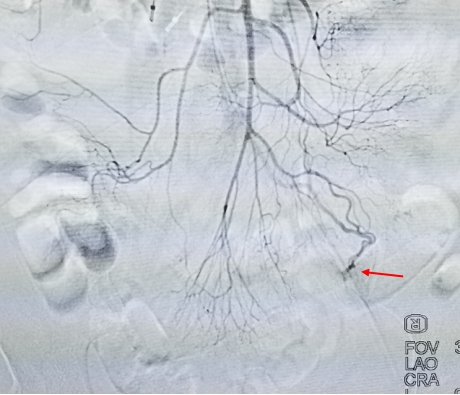

通过介入血管腔内技术,发现花生米大小的血管畸形

手术如期进行,花生米大小的出血部位被找到,通过留置在病变部位的导管进行术中精确定位,病变肠管顺利切除,患者的多年出血顽疾得到治愈。